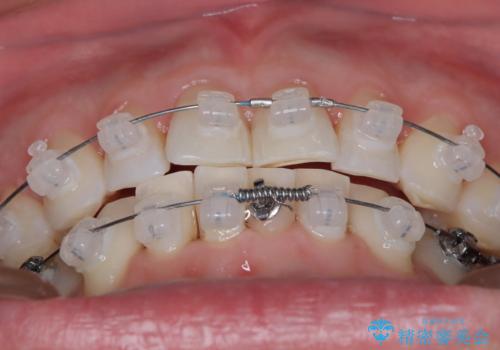

定期健診で歯並びを相談 セラミックブラケットでのワイヤー矯正例

- インシグニア デイモンクリア

- 治療計画

- 定期健診の際に、下顎前歯のガタつきが年々悪化しているとの相談を患者様より頂戴しました。下顎前歯の叢生(ガタつき)程度や患者様の希望もあり、非抜歯でも無理のない範囲と考えワイヤー矯正にて治療計画を立案しました。着色の少ないセラミックブラケットを使用しています。

日常生活において歯は1本ずつ独立した動きをします。コンタクト部分(隣の歯と触れ合っている接触点のこと)が擦り減っていくことで、一般に歯は少しずつ前歯の方に傾斜していきます。要因は様々ですが、このことにより特に前歯において叢生(ガタつき)の程度が大きくなっていくことが考えられます。他にも、歯周組織の状態も歯の配列に大きな影響を与えます。ワイヤー矯正中はブラッシングの難易度が上がりますが、磨きにくい部分は毎回診療中に患者様と一緒に鏡を見ながら確認しました。